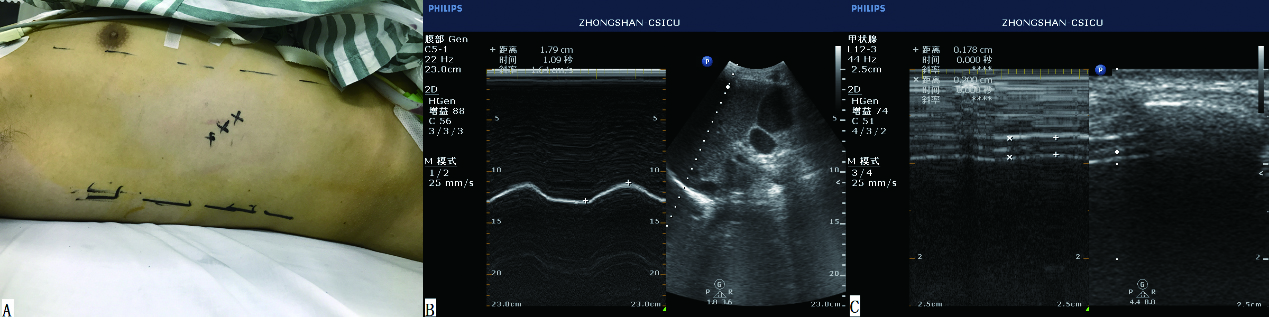

1.2 膈肌功能测量方法超声机器型号为飞利浦CX50,由有超声资质的同一位监护室医生测量。测量方法为:腹部探头测量双侧膈肌活动度,再通过血管探头测量双侧膈肌厚度,并计算膈肌厚度随呼吸运动发生的变异率。膈肌厚度变异率=(吸气末厚度-呼气末厚度)/呼气末厚度。具体方法为首先应用2D模式在腋前线或腋中线找到最佳测量路径(探头位置见图 1),然后选择M超测量膈肌位移或厚度。膈肌功能不全的定义为一侧膈肌活动度小于10 mm,或呈负向运动。负向运动指反常呼吸运动。

| 图 1 膈肌位移及厚度测量: A:超声探头置于左侧或右侧腋中线,两肋骨中间;B、C:M超显示膈肌位移及厚度 Figure 1 Measurement of diaphragm excursion and thickness:A: The probe was placed on the lower intercostal spaces of the midaxillary line. B and C: M model revealed the excursion and thickness of the diaphragm |